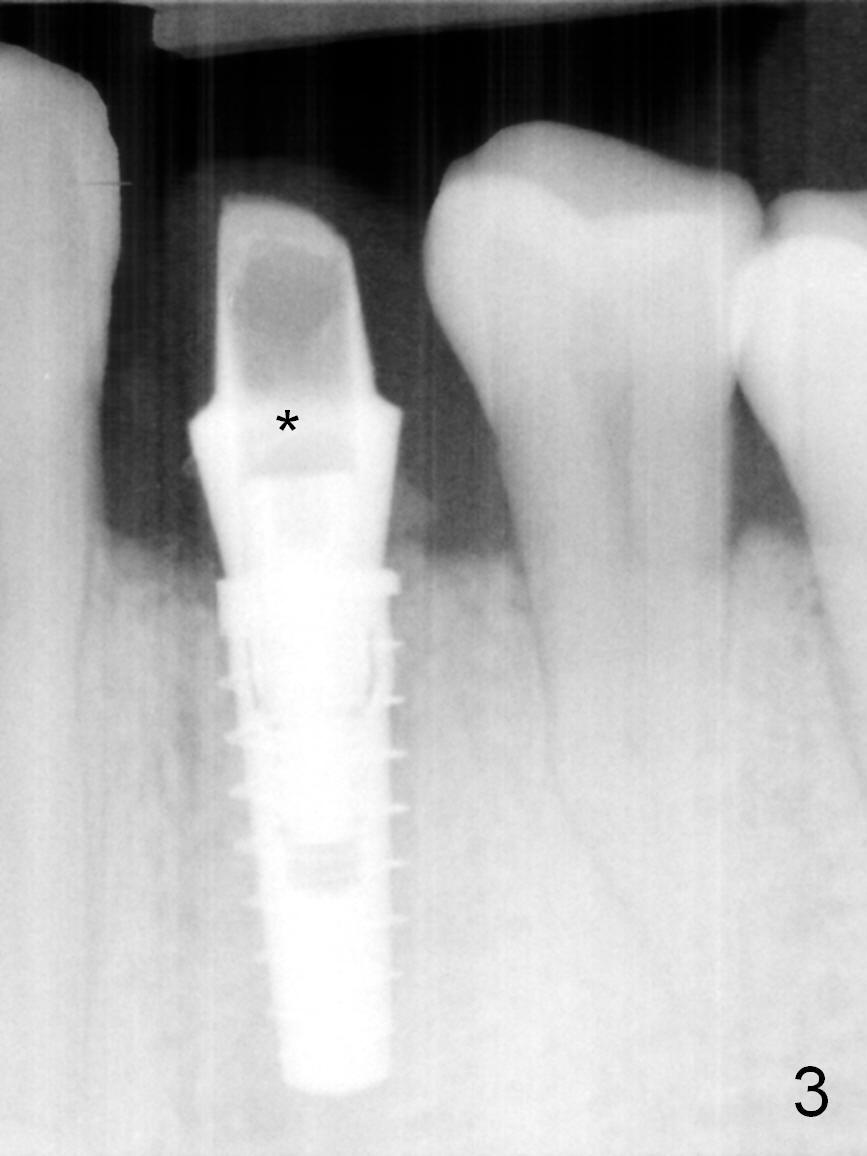

The residual root at #21 seems to be buccally positioned (Fig.1 *).  The initial osteotomy is established with the 1.6 mm drill at 11 mm (Fig.2).  Later the depth increases to 13 mm.  The initial osteotomy is found to be too lingual, but experience shows that as osteotomy increases in diameter, the trajectory would shift buccally due to the thick lingual plate (slope).  When 3.3 mm Magic drill reaches 11 mm, the patient feels pain.  It is probably due to the dense bone.  A 4x11 mm IBS implant cannot be seated due to high torque; it is removed.  The osteotomy is increased with 3.8 mm drill.  The implant is re-seated with >55 Ncm; it is over-lingually placed.  Due to failure to seat the implant driver completely, the implant cannot be un-torqued.  A 4.5 mm 15° angled abutment (3 mm cuff) is placed for immediate provisional (Fig.3,4 *).